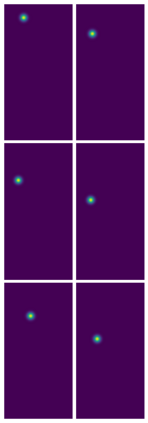

Angular measurements is essential to make a resonable treatment for Hallux valgus (HV), a common forefoot deformity. However, it still depends on manual labeling and measurement, which is time-consuming and sometimes unreliable. Automating this process is a thing of concern. However, it lack of dataset and the keypoints based method which made a great success in pose estimation is not suitable for this field.To solve the problems, we made a dataset and developed an algorithm based on deep learning and linear regression. It shows great fitting ability to the ground truth.